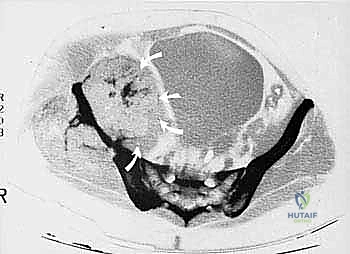

* CT with Intravenous Contrast and 3D Reconstruction (FIG 3): This is our workhorse for assessing bone involvement, destruction, and the critical relationship between the tumor and major pelvic blood vessels. It reveals any distortion of the pelvic anatomy and guides resectability. Figure 3A clearly shows extensive bone destruction and tumor extension into the pelvis and gluteal region. Figure 3C highlights an extensive tumor on the medial aspect of the ilium with destruction of the inner table.

- Defining Resection Margins: "We've marked our osteotomy lines based on our CT and MRI scans, ensuring adequate oncologic margins. For this periacetabular chondrosarcoma, we're performing an extensive resection."

- Initial Cuts: "We'll start with the iliac wing osteotomy. Use a large oscillating saw or Gigli saw, under constant visual and fluoroscopic guidance, to make the superior cut through the ilium, staying well clear of the sacroiliac joint."